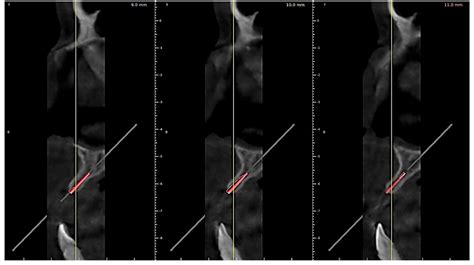

» Gallery 6-Immediate Dental Implant placement in a periodontaly ...

Gallery 6-Immediate Dental Implant placement in a periodontaly weakened ...

drmurugavel.in